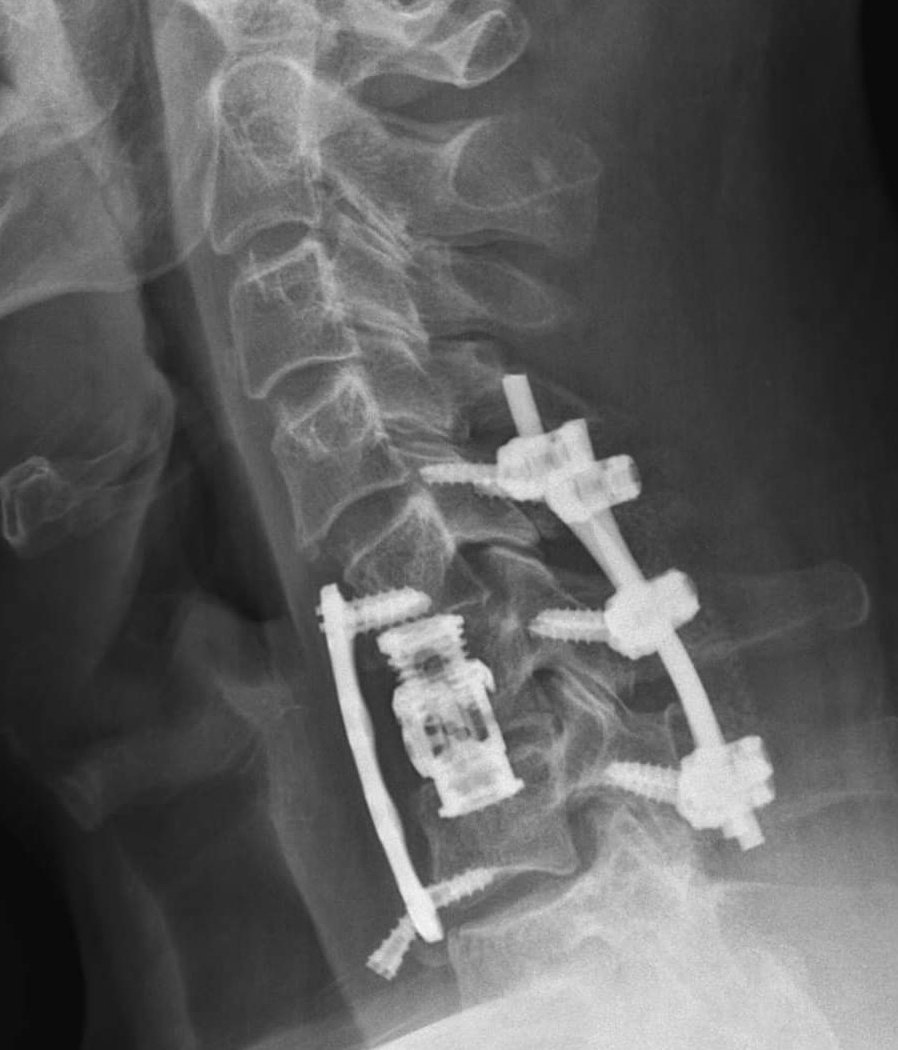

Vandaag 5 jaar terug brak ik mijn nek tijdens een Teamevent, 7 maanden recovery en een echtscheiding later sta ik er nog steeds #whatdoesntkillyou